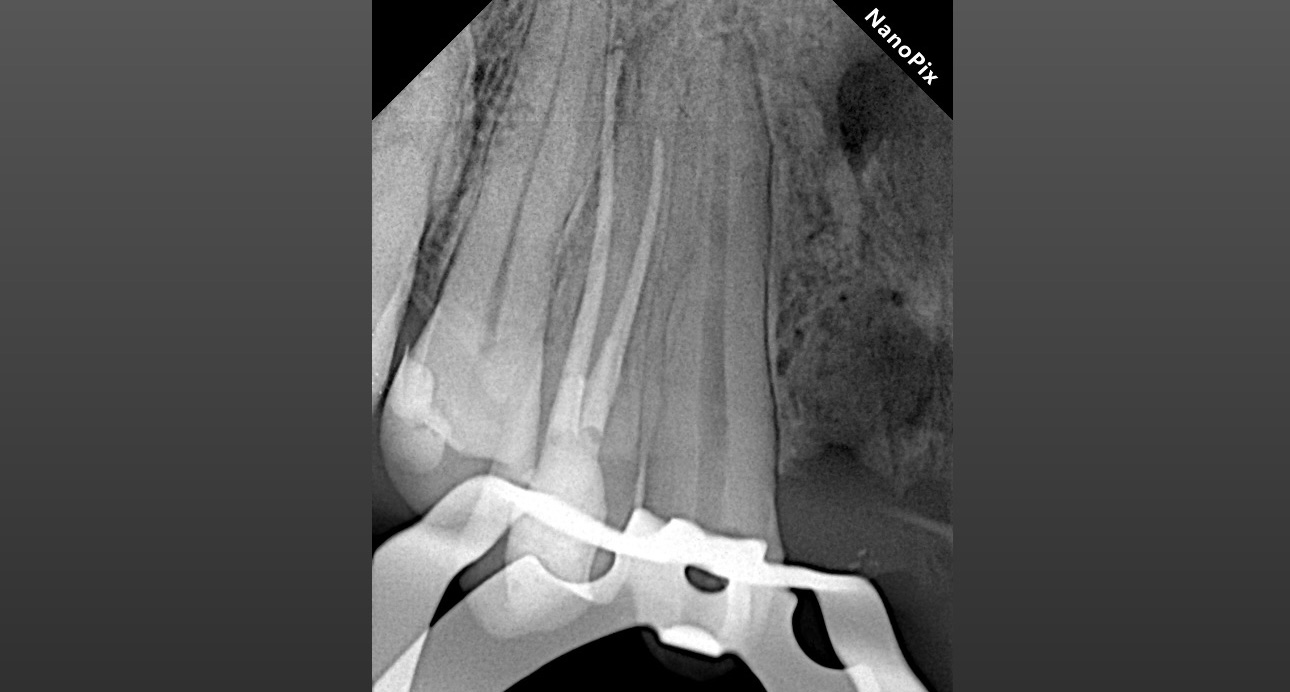

Обтурация биокерамическим силером с гуттаперчей. Автор: Диана Кипарисова

Инструментация Soco SC до 45/04. Финишный инструмент до чистых опилок на кончике файла.

Ирригация 3% NaOCl с УЗ активацией + 17% ЭДТА.